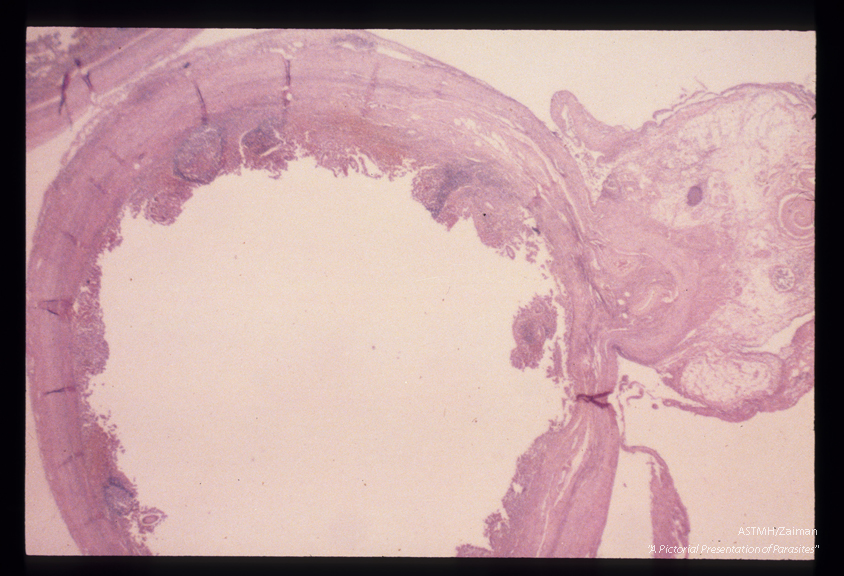

Adult male in the mesoappendiceal vein. The parasite is seen as a coiled object in the upper right hand corner. No ova were seen in the appendix itself.

Schistosoma mansoni

Description: Adult male in the mesoappendiceal vein. The parasite is seen as a coiled object in the upper right hand corner. No ova were seen in the appendix itself.